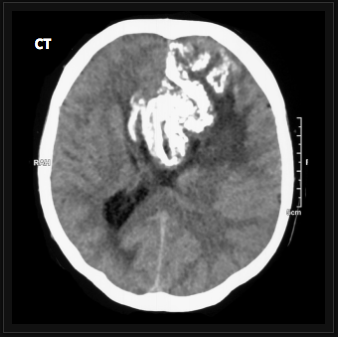

Histopathologic examination of which brain tumor will show areas of calcification, cyts, and necrosis?

Oligodendroglioma